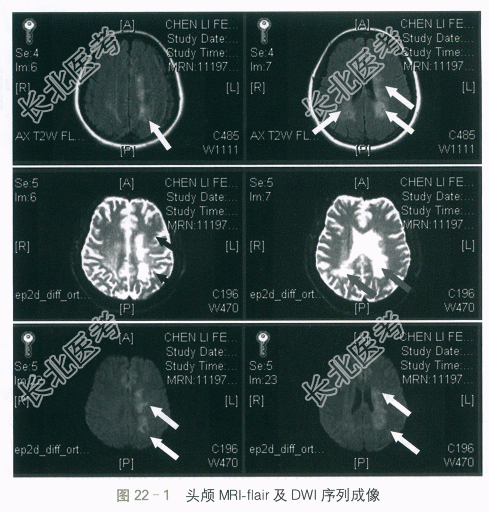

(2)影像学检查:①视觉诱发电位:双眼视觉诱发电位P100波未引出。②视野检查:双眼颞部视野缺损。③头颅MRI:双侧脑室旁可见多发斑片状长T1长T2信号灶,flair呈高信号,DWI呈高信号,病灶与侧脑室方向垂直。增强后可见点片状强化。脑室系统未见异常,中线结构居中。考虑:两侧脑室旁多发MS,以枕角旁为著,如图22-1所示。④颈椎MRI:颈髓未见异常信号。⑤胸椎MRI:胸椎MRI平扫胸髓未见明显异常。